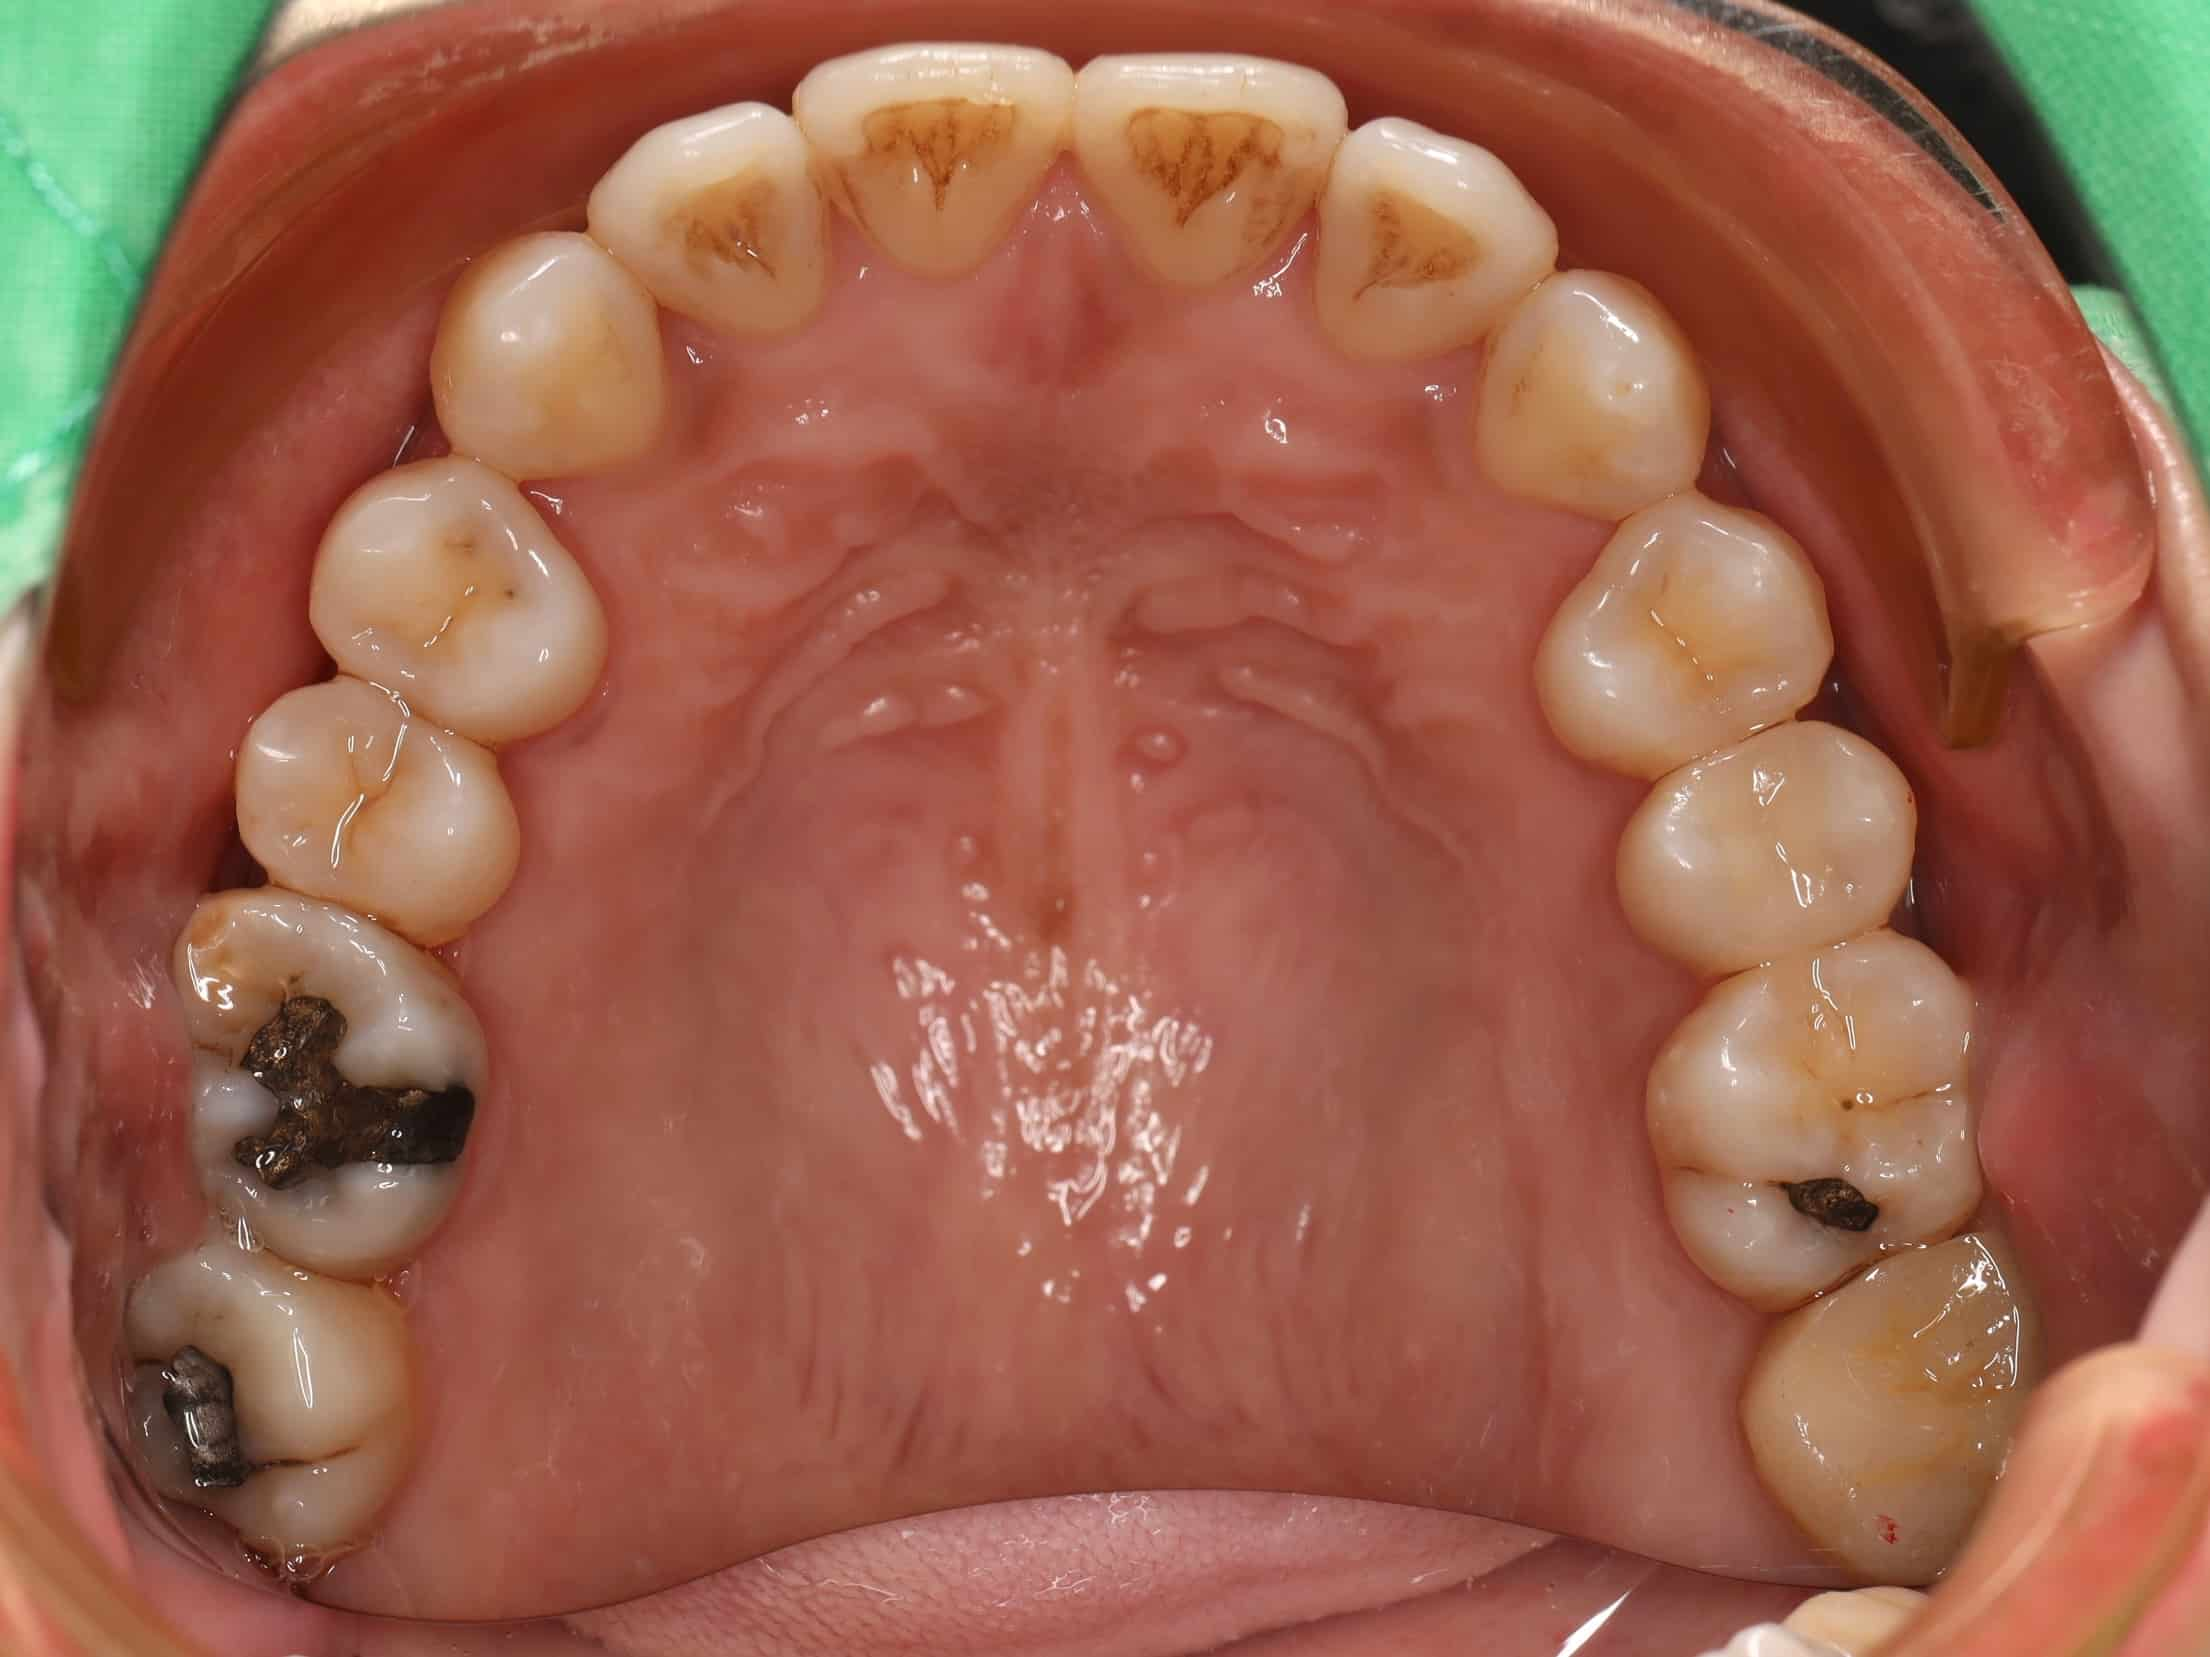

古小姐第一次來到診間時,主要是希望能做全口的詳細評估與檢查,因為她進食較黏稠的食物,牙齒容易感到疼痛,刷牙的時候容易出血,更令她困擾的問題是,她以前因為蛀牙拔掉牙齒,但沒有進行後續處理,左下方有缺牙的情況,除了導致牙齒開始出現縫隙,長期習慣用右邊進食,也讓她兩邊咬合都不太舒服。

經過全口檢查與評估後,我們發現古小姐的口腔問題相當複雜,主要可以歸納為以下幾個項目:

全口牙周病問題 - 導致刷牙時流血的主因

左邊缺牙問題 - 長期缺牙導致排列與咬合問題

咬合與牙縫問題 - 影響整體美觀與功能

我們首先進行最基本的牙周治療,控制發炎狀況,並處理蛀牙問題,為後續治療奠定良好基礎。